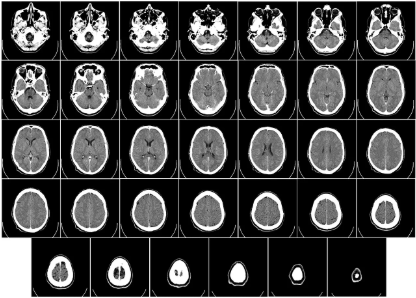

현대 의료 진단의 핵심 장비인 컴퓨터 단층 촬영기, CT는 지난 수십 년간 비약적인 발전을 거듭하며 현대 의학 진단의 필수 장비로 자리 잡았습니다. 과거에는 상상조차 할 수 없었던 빠르고 선명하며 정밀한 영상을 이제는 당연하게 얻고 있죠. 이러한 CT 발전의 숨은 주역 중 하나는 바로 X선 정보를 포착하는 검출기(Detector)입니다. 그리고 이 검출기 기술의 눈부신 진화 여정에는 반도체 기술이 핵심 동력으로 작용해 왔습니다.

최초의 CT 시스템이 개발되었을 때, 검출기 기술은 지금과 비교하면 기초적인 수준이었습니다. 당시 검출기들은 X선이 특정 기체를 이온화시키는 과정에서 발생하는 전기 신호를 감지하는 방식 등, 비교적 기초적인 물리 원리를 이용했습니다. 이러한 방식의 검출기는 X선 신호를 전기 신호로 변환하는 속도가 느리고, 감지할 수 있는 X선 양(효율성)이 제한적이었으며, 측정된 데이터를 정밀하게 처리하는 능력도 부족했습니다.

결과적으로 초기 CT는 스캔 시간이 매우 오래 걸리고, 영상의 해상도와 품질 또한 현재 수준에 미치지 못했습니다. 이는 CT 기술이 임상 현장에서 더 폭넓게 활용되기 위한 '속도'와 '정밀도'라는 중요한 한계에 직면했음을 의미했습니다. 새로운 돌파구가 필요한 시점이었습니다.